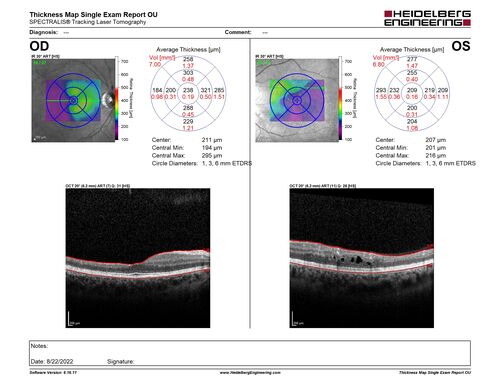

Coats Plus Syndrome - Cerebroretinal microangiopathy with calcifications and cysts (CRMCC)

38 year old female CTC1 positive with Coats Plus Syndrome. This case was published https://pmc.ncbi.nlm.nih.gov/articles/PMC10649444/